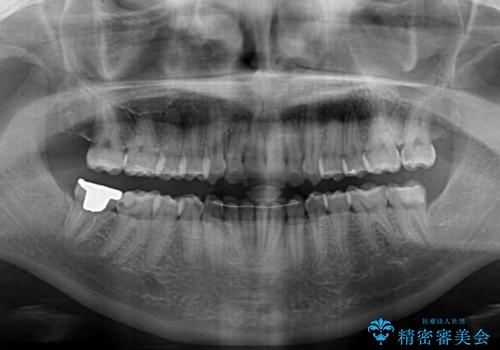

骨格的に左右にずれいている 前歯のデコボコをインビザラインで解消

- 前歯のデコボコと八重歯を気にして来院された患者様です。

叢生の程度は中等度であったため、IPR(歯と歯の間を削る)と歯列の側方拡大をメインに、インビザラインを用いて歯列を改善することとしました。

また、下顎骨の右側変位による右側臼歯の咬合を改善させるよう試みることとしました。

右側の咬合改善を目標に様々な手法を用いましたが、骨格的なズレによる不正咬合はインビザラインでは改善することができませんでした。